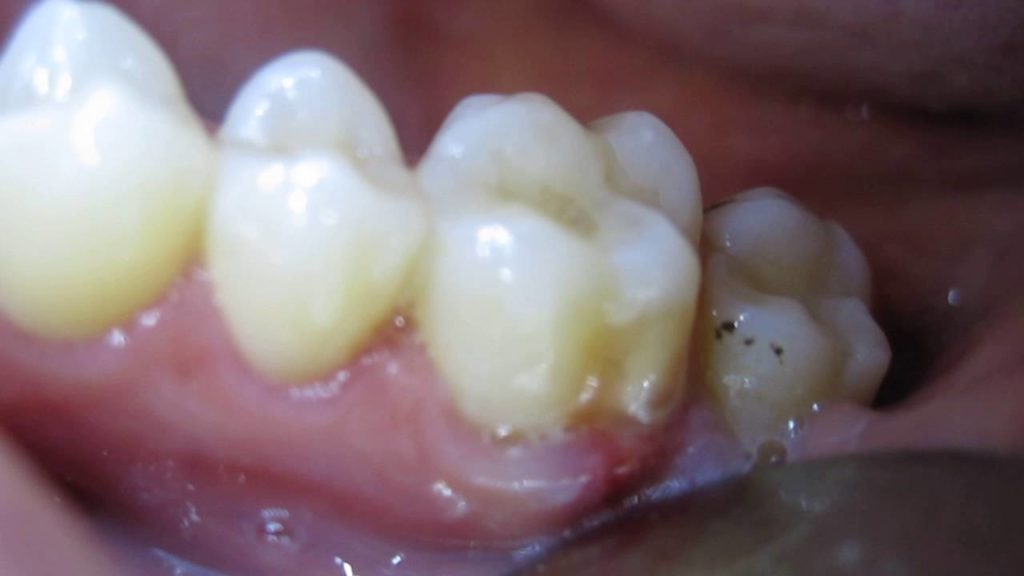

home Health Concerns Disgusting Pus-Filled Tooth Gum Boil (Periodontal Abscess) Disgusting Pus-Filled Tooth Gum Boil (Periodontal Abscess) By dentists Posted in Health Concerns Posted on June 21, 2017